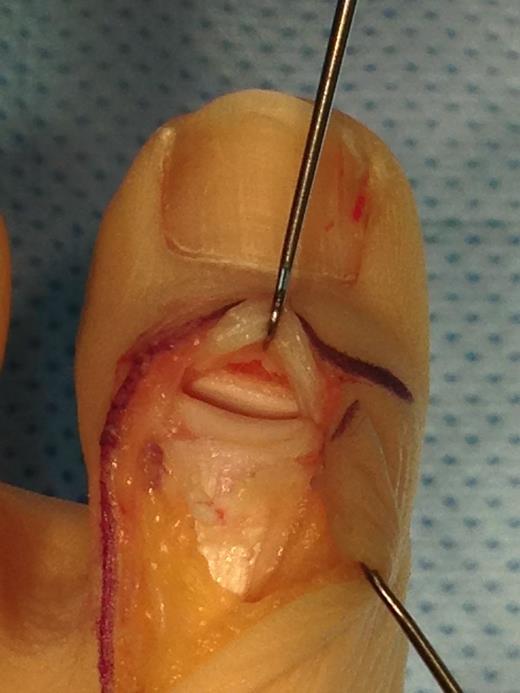

Under general anaesthesia, an L-shaped incision was made to avoid the dorsomedial sensory nerve and avoid injury to the germinal matrix of the nail. The EHL tendon was found to be completely ruptured from the distal phalanx and had retracted back towards the MTPJ. The tendon end was debrided back to healthy tissue and was secured back to the distal phalanx using a Mitek anchor and a non-absorbable suture in a modified Krakow technique. The IPJ was stabilized with a 1.2-mm Kirschner wire (Figs 3–5).

Operative photograph showing transfixion of the IPJ with a K-wire and insertion of a Mitek anchor into the distal phalanx.